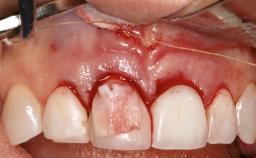

Mauricio Araujo and Flauvia Matarazzo present this straightforward clinical case, demonstrating the potential effect of implant placement depth on the resolution of peri-implant treatment. A 42-year-old systemically healthy female patient, a non-smoker with no history of periodontitis, was treated at the Dental Clinic at the State University of Maringá, Brazil between 2008 and 2009, when she received five implants restored with single crowns at sites 14, 26, 27, 36, and 46. After delivery of the implant-supported prosthetic restorations, the patient was enrolled in the supportive peri-implant therapy (SPiT) maintenance program at the same university.